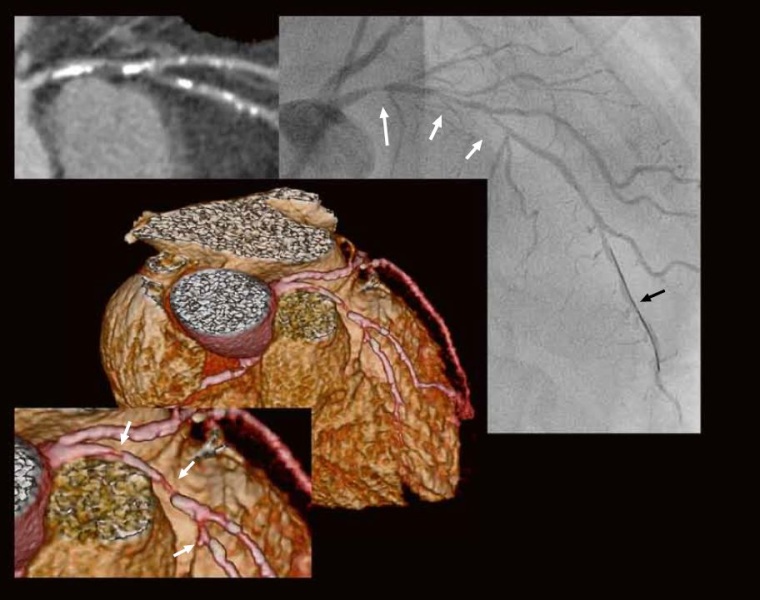

Fall 3

Anamnese:

76-jähriger Mann, in letzter Zeit zunehmend retrosternales „Krampfgefühl“ beim strammen Spazierengehen oder bei psychischem Stress.

Kardiovaskuläre Risikofaktoren:

arterielle Hypertonie, unter Therapie Ruhe-Blutdruck: 139/72 mmHg, Diabetes mellitus Typ II, positive Familienanamnese, Lipidprofil: Gesamt-Cholesterin: 174 mg/dl, LDL-Cholesterin: 100 mg/dl, HDL-Cholesterin: 46 mg/dl, Triglyzeride: 140 mg/dl.

CT -Angiographie:

in der Curved MPR (oben links) schwere kalzifizierte und nicht-kalzifizierte Plaquebildung (Gesamt-Agatston-Score = 884, d. h. hohes Risiko). In der 3D-Rekonstruktion (Mitte und Vergrößerung unten links) und in der Curved MPR (oben links) dringender V. a. hochgradige serielle LAD-Stenosen (weiße Pfeile) vor und nach dem RD1-Abgang. In der invasiven Koronarangiographie (rechts schon mit liegendem Führungsdraht, schwarzer Pfeil) ebenfalls Darstellung dieser Stenosen im proximalen und mittleren RIVA (weiße Pfeile). Strahlendosis CTA = 1,6 mSv.

Therapie:

Revaskularisation des RIVA mit PTCA und Stent-Implantation in den proximalen RIVA. Optimierung des kardiovaskulären Risikoprofils.